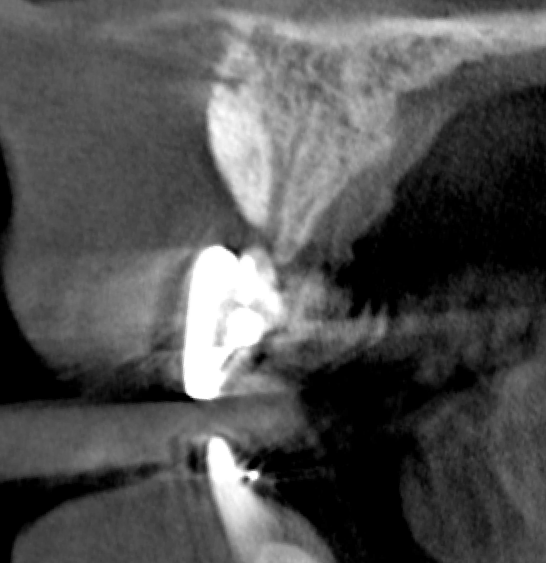

Tomographic images revealed a large tridimensional defect, with vertical and horizontal loss of bone extending to the apical third of teeth Nos. 6 and 8. Additionally, a buccal bone dehiscence was evident on tooth No. 5, and thin labial plates secondary to the orthodontic movement were present in several areas (Figure 3 and Figure 4).

Fig 3. Tomographic images revealed a tridimensional defect extending to the apical third of teeth Nos. 6 and 8, a buccal bone dehiscence on tooth No. 5, and associated thin labial plates.

Figure 3

Fig 4. Tomographic images revealed a tridimensional defect extending to the apical third of teeth Nos. 6 and 8, a buccal bone dehiscence on tooth No. 5, and associated thin labial plates.

Figure 4